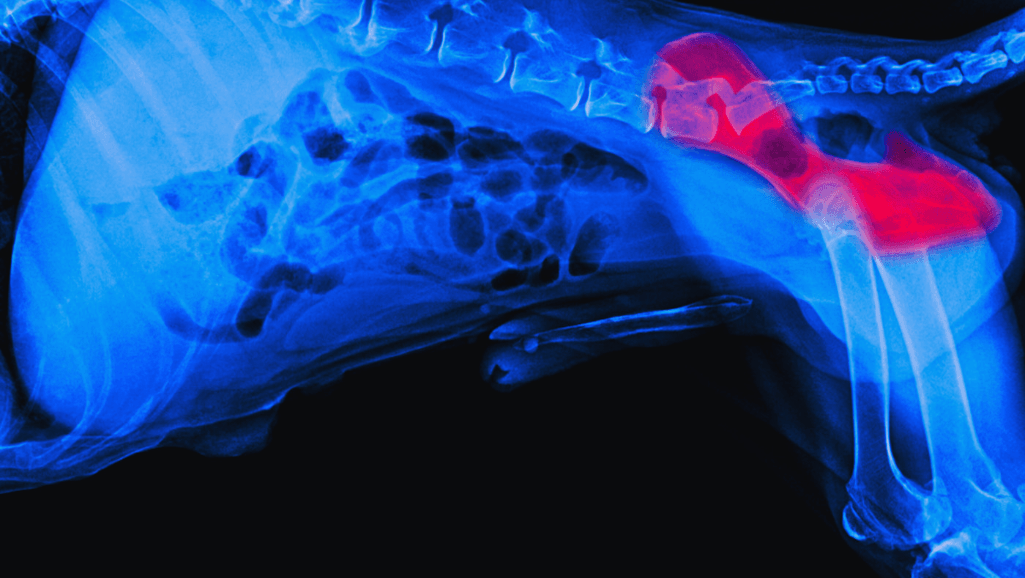

The hip joint is a ball and socket joint, with the ball located at the top of the femur (thigh bone) and the socket situated in the pelvis. In dogs with hip dysplasia, the ball and socket do not fit or develop properly. As a result, the joint experiences increased friction and stress, leading to the gradual deterioration of the joint structures.

Here is a representation of the hip joint anatomy: